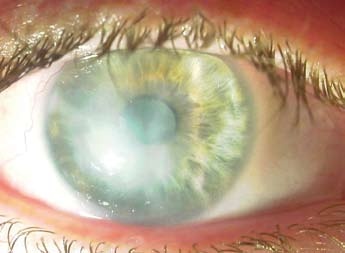

Nález při příjmu: PO: víčka oteklá, červená, bulbus výrazně podrážděn, smíšená injekce, sekrece, rohovka zbělená s erozí v centru, v přední komoře bělavé hmoty, zornice miotická, dále nelze hodnotit. Dle UZ B scan – sklivcový prostor čistý. (obr. 2)

Vizus: pohyb, certa. Nitrooční tlak v normě.